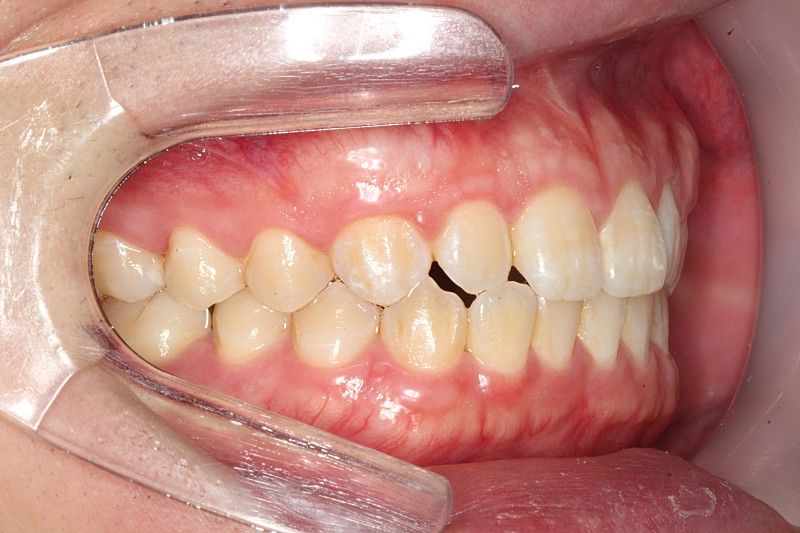

정상 범위입니다. 다만 오른쪽 작은 앞니(측절치)는 아랫니가 앞으로 나온 반대교합 입니다.

앞니 교합이 좋진 않으신거 같습니다. 왼쪽치아들은 그래도 잘 물리는데 오른쪽 치아들의 교합이 좋진 않네요.